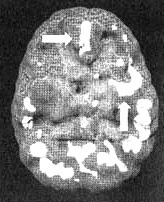

Мозг Марка. Агрессивность

Иллюстрация к книге — Измените свой мозг - изменится и жизнь! [i_084.jpg]

Трехмерное изображение снизу — активный мозг. Обратите внимание на выражение пониженную активность особенно в левой височной доле (стрелка).